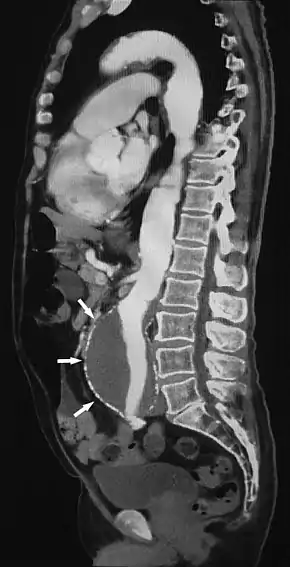

![]() Sagittal thin slice of a computed tomography angiography abdominal aortic aneurysm (AAA) (arrows) | |

Aorta and great arteries

CTA can be used in the chest and abdomen to identify aneurysms in the aorta or other major blood vessels. These areas of weakened blood vessel walls that bulge out can life-threatening if they rupture. CTA is the test of choice when assessing aneurysm before and after endovascular stenting due to the ability to detect calcium within the wall.[2] Another positive of CTA in abdominal aortic aneurysm assessment is it allows for better estimation of blood vessel dilation and can better detect blood clots as compared to standard angiography.[3]